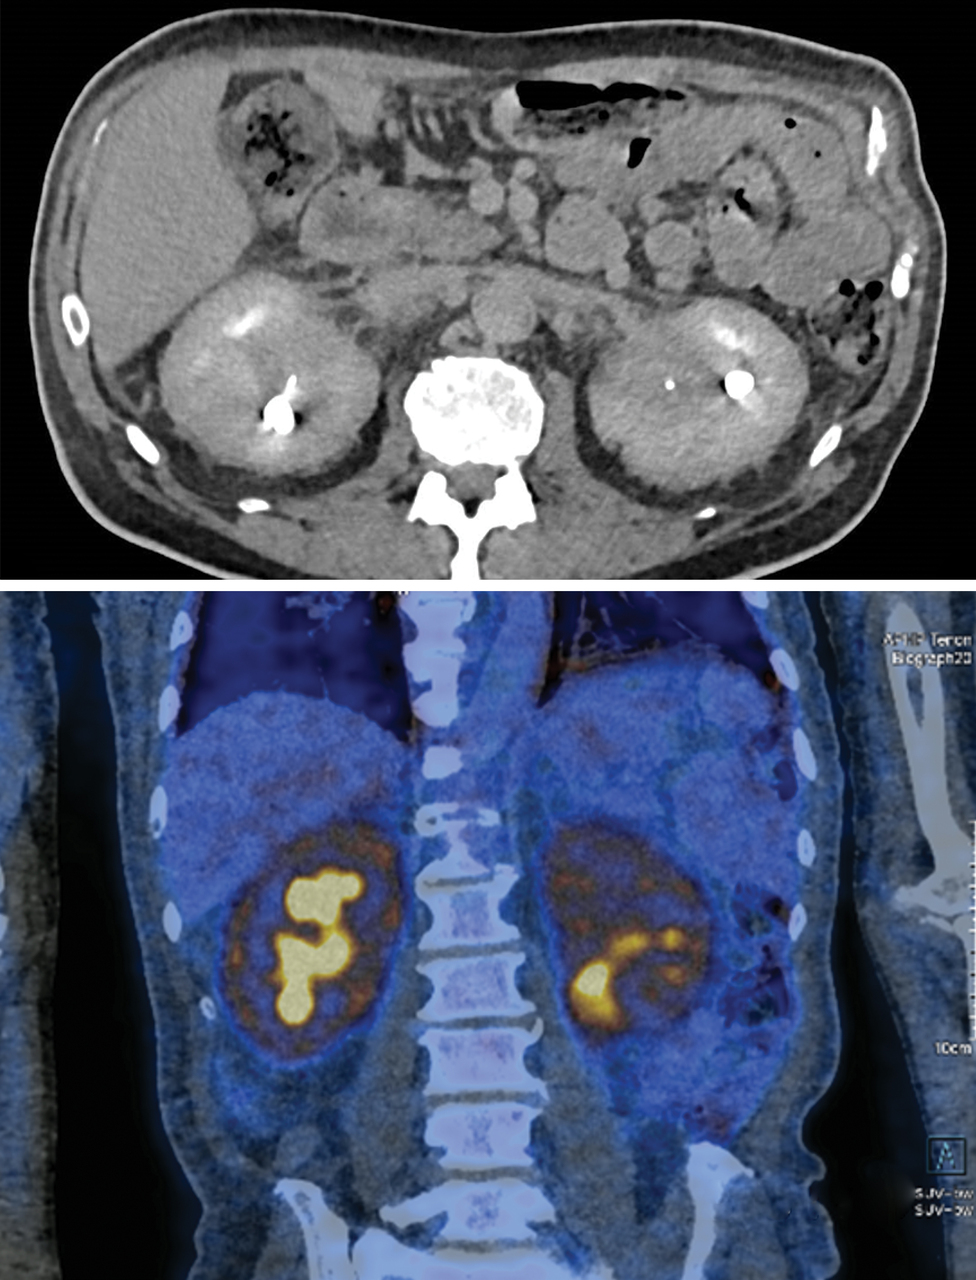

Un scanner puis une tomographie par émission de positons couplée à un scanner (TEP scan) sont réalisés.

L'infiltration de la graisse périrénale donne un aspect de « rein chevelu ».